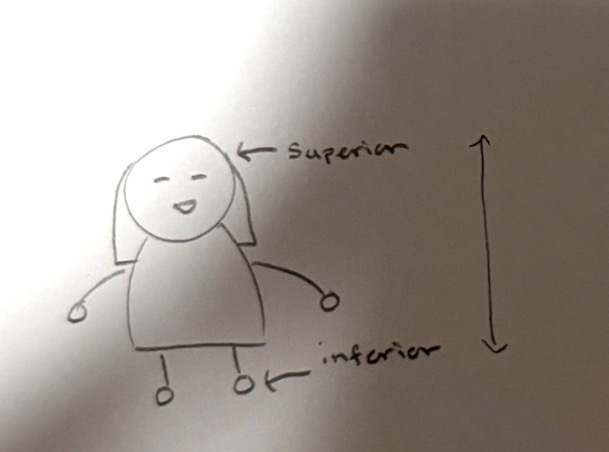

Superior

closer to the top of the body (standing up straight)

Inferior

below a body part or structure (standing up straight)